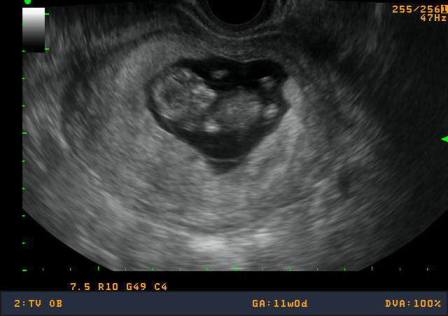

Voltunk ma dokinál... búcsút mondtunk a Kaálinak...

És itt van Kismóki legújabb sztárfotója... :lol: